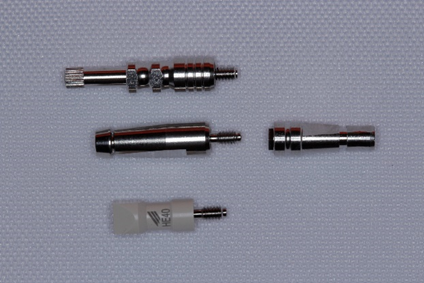

Vale ressaltar também que os pilares do tipo UCLA podem apresentar o dispositivo antirrotacional indicado para casos de coroas unitárias ou dispositivo sem antirrotacional indicado aos casos de próteses múltiplas. Lembrando que a Implacil De Bortoli disponibiliza os componentes UCLA para as conexões de HE, HI e CM, como ilustrado na Figura 3.

Abaixo, temos as principais características do pilar UCLA:

– componente existente para as conexões de HE, HI e CM da Implacil De Bortoli;

– componente existente em três formas para HE/HI: plástico, plástico + base metal, metálico;

– componente existente em duas formas para CM: plástico + base metal e metálico;

– UCLA metálico – indicado para confecção de coroas provisórias;

– UCLA plástico – indicado para processo de fundição;

– UCLA plástico + base de metal – indicado para processo de sobrefundição;